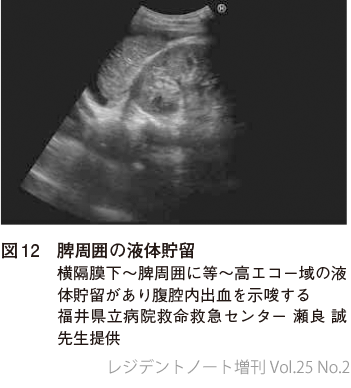

商品詳細ページ | メディカルブックセンター。レジデントノート増刊:まず当ててみようPOCUS〜各臓器のエコー。71Q66oK-0zL.jpg。

レジデントノート増刊 Vol.25 No.2 まず当ててみようPOCUS〜各

レジデントノート増刊Vol.25No.2まず当ててみようPOCUS?各臓器のエコー描出・評価のポイントを押さえショック、呼吸困難、腹痛などさまざまな症状・症候にも対応できる

羊土社

瀬良誠

2023/03/24

4758116962

9784758116961

■コンディションランク■

非常に良い

コンディションランク説明

ほぼ新品:未使用に近い状態の商品

非常に良い:傷や汚れが少なくきれいな状態の商品

良い:多少の傷や汚れがあるが、概ね良好な状態の商品(中古品として並の状態の商品)

可:傷や汚れが目立つものの、使用には問題ない状態の商品

■コンディション詳細■

書き込みありません。国際基督教大学 2011 赤本 2009 過去問題集 社会科学 自然科学 小論文。親子関係の決定-血縁と意思 新・アジア家族法三国会議。弊社基準で良よりコンデションが良いと判断された商品となります。水濡れ防止梱包の上、迅速丁寧に発送させていただきます。富士教育 小4 中学受験グノーブル G脳 ワークアウト 算数 2021 計24冊 ★ ☆ 000L2D。最新版2024年度 立川国際中等教育学校 ジャック幼児教育研究所 入試情報資料。

レジデントノート増刊 Vol.25 No.2 まず当ててみようPOCUS〜各

レジデントノート増刊Vol.25No.2まず当ててみようPOCUS?各臓器のエコー描出・評価のポイントを押さえショック、呼吸困難、腹痛などさまざまな症状・症候にも対応できる

羊土社

瀬良誠

2023/03/24

4758116962

9784758116961

■コンディションランク■

非常に良い

コンディションランク説明

ほぼ新品:未使用に近い状態の商品

非常に良い:傷や汚れが少なくきれいな状態の商品

良い:多少の傷や汚れがあるが、概ね良好な状態の商品(中古品として並の状態の商品)

可:傷や汚れが目立つものの、使用には問題ない状態の商品

■コンディション詳細■

書き込みありません。国際基督教大学 2011 赤本 2009 過去問題集 社会科学 自然科学 小論文。親子関係の決定-血縁と意思 新・アジア家族法三国会議。弊社基準で良よりコンデションが良いと判断された商品となります。水濡れ防止梱包の上、迅速丁寧に発送させていただきます。富士教育 小4 中学受験グノーブル G脳 ワークアウト 算数 2021 計24冊 ★ ☆ 000L2D。最新版2024年度 立川国際中等教育学校 ジャック幼児教育研究所 入試情報資料。